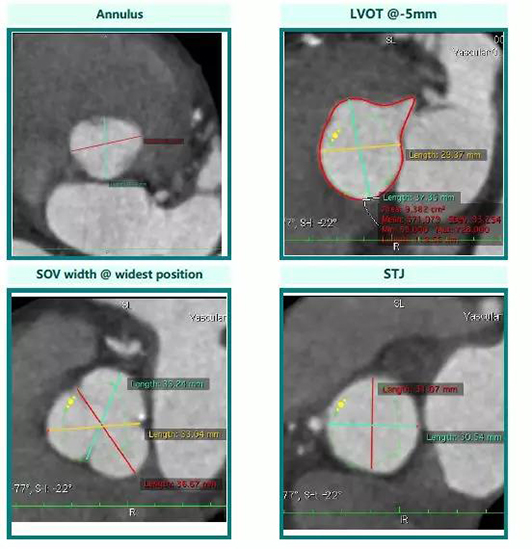

由于患者年龄大,心功能差,经常咳嗽、咳痰。传统的体外循环手术风险极大,而单纯的药物治疗效果欠佳,随着病情的发展,如果再不进行积极干预,患者的心功能及生活质量会越来越差,甚至危及患者生命。邹承伟主任带领的TAVI团队在通过药物治疗改善患者心功能的同时,积极进行术前准备,通过心脏超声及心脏大血管CT检查对患者进行全方位评估,并对CT进行细致入微的分析,最终决定采用29mmJ-Valve介入瓣膜行经心尖主动脉瓣植入术(TAVI手术),即经患者左侧胸壁开一4-5cm小口,将一根细长的导管经心尖穿刺送入心腔,在透视下通过特定的瓣膜装载释放系统完成主动脉瓣的定位与释放。为保证手术的顺利进行,手术前一天,TAVI团队成员便就手术预案、手术中可能出现的各种问题及处理措施、手术器材配备摆放、麻醉与监护、术后管理等各个方面进行了周密部署及演练。